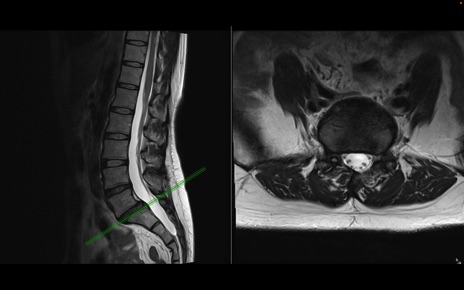

腰椎MRI

T2WI(横断像)

T2WI(矢状断像)